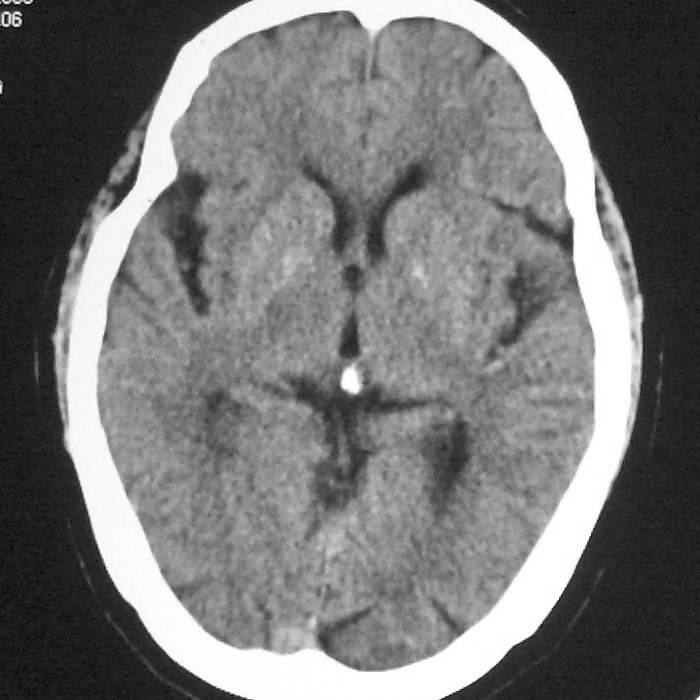

f,70y,口角歪斜、流涎、吐词不清三天

症状这么明显的话一般不会是单纯面神经麻痹引起的,最好做个mri,如果确实没有问题的话才能考虑面神经麻痹,毕竟这两种病的治疗和预后不一样,这个病人还有脑白质疏松。

左侧半卵圆中心腔梗应当比较明确,右侧基底节好象不明显,不好说,做个mri明确吧

双侧多发腔梗

右侧基底,左侧半卵圆中心腔梗

1、右侧基底,左侧半卵圆中心腔梗。2脑萎缩。

具体位置我认为应该写左侧放射冠腔梗

左侧半卵圆中心,右侧基底节腔梗。再加个脑萎缩吧

双侧多发腔梗 脑萎缩